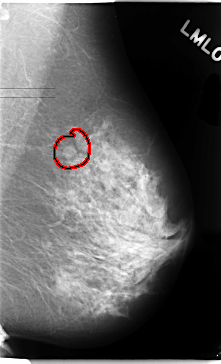

C_0102_1.LEFT_MLO

LEFT_MLO LINES 4728 PIXELS_PER_LINE 2872 BITS_PER_PIXEL 12 RESOLUTION 50 OVERLAY

FILE: C_0102_1.LEFT_MLO.OVERLAY

TOTAL_ABNORMALITIES 1

ABNORMALITY 1

LESION_TYPE MASS SHAPE OVAL MARGINS CIRCUMSCRIBED

ASSESSMENT 3

SUBTLETY 5

PATHOLOGY BENIGN

TOTAL_OUTLINES 1

BOUNDARY